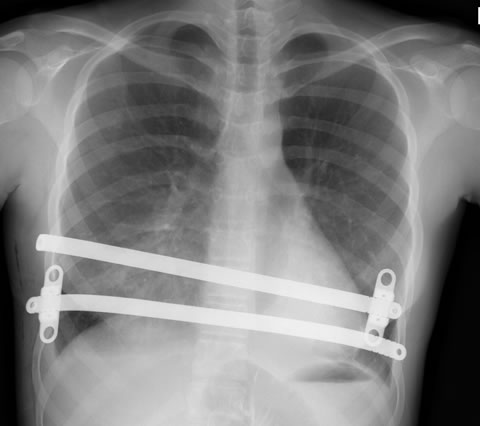

Post operative chest x-ray from the side (left) and the front (right) with 2 pectus bars in position. Sometimes 2 pectus bars are required to obtain the best cosmetic result.